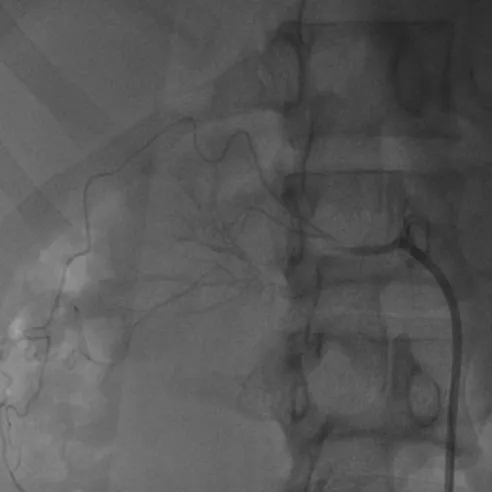

经过周密评估,团队制定了精细的介入手术方案,并特邀北京专家指导,由济南市中心医院高血压科介入团队关玉庆、孔庆赞、刘淼主任共同施术。术中造影证实了术前判断:右肾动脉中远段血栓形成、血管近乎闭塞。在精准操作下,导丝顺利通过闭塞段,经球囊扩张后,血流恢复通畅。

术前右肾动脉近乎闭塞